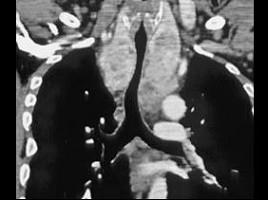

男,67岁,呼吸困难半年余,请结合影像学检查,选出最可能的诊断 ( )A、纵隔畸胎瘤B、胸腺瘤C、淋巴瘤D、间皮囊肿E、胸骨后甲状腺肿

问题 男,67岁,呼吸困难半年余,请结合影像学检查,选出最可能的诊断 ( )

选项 A、纵隔畸胎瘤 B、胸腺瘤 C、淋巴瘤 D、间皮囊肿 E、胸骨后甲状腺肿

答案 E